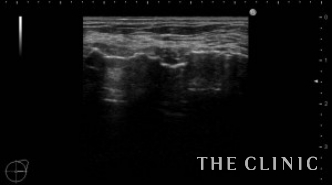

この方は2年前に他院にてバッグ抜去+脂肪注入(片側400㏄)を受けられています。その際、被膜の中に脂肪が入ってしまい血流が途絶えたために脂肪壊死となりしこりになってしまったようです。一番大きい物で6㎝の充実性のしこりがありました。(左の画像)その他にもオイル状の小さいしこりがいくつかあり、皮下にあるものは針で刺してオイルを吸引除去しました。(右の画像)

6㎝のしこりの被膜は肥厚し、内部は充実性のしこり(脂肪壊死)とオイルの両方を認めます。肥厚した被膜を破りチューメセント(麻酔)を注入して、脂肪壊死を崩すためベイザーリポを使用します。

脂肪が崩れた後は吸引を行い、しこりは消失しました。右側は吸引除去した壊死脂肪です。